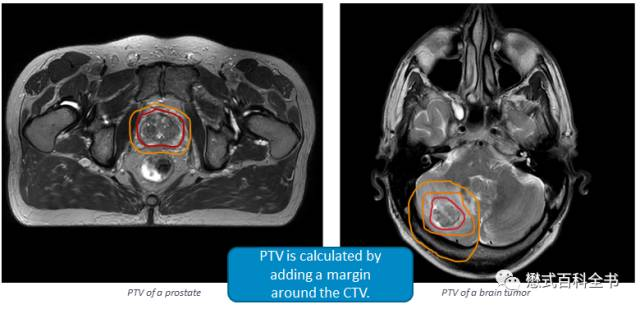

PTV(Planning Target Volume), 计划靶区:做放射治疗计划时勾画的一个体积区,计划靶区必须要保证放射治疗线准确地定点到临床靶区上。PTV>CTV>GTV。